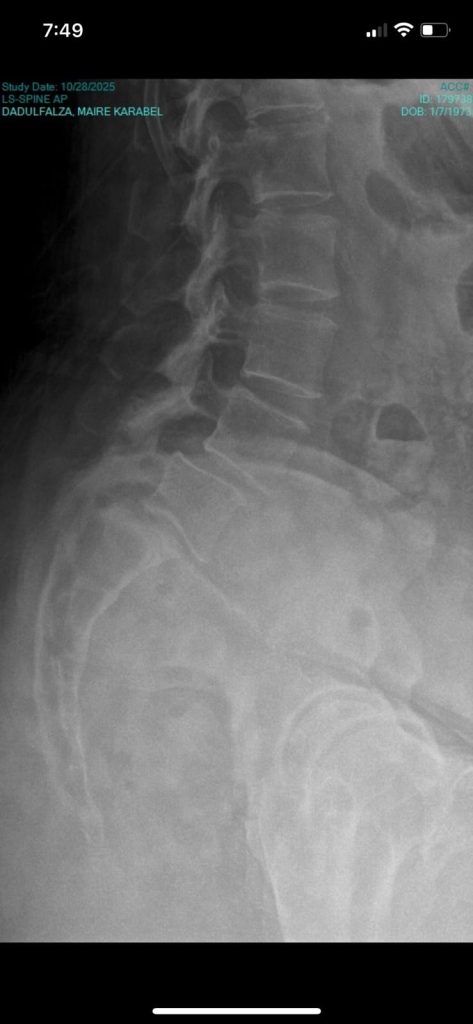

Since May 2025, my spine issues have escalated. After my first surgery last June 27, the disc extrusion came back — more painful, more stubborn. On November 4, 2025, I underwent spine fusion surgery. It wasn’t part of the plan, but it became the only way forward.

What was supposed to be a 5–6 hour operation stretched past ten. I lost more blood than expected — more than what could safely be transfused. In the middle of it all, Dr. Dadz made a difficult call: to stop at two levels instead of the recommended three.

That decision saved my life.